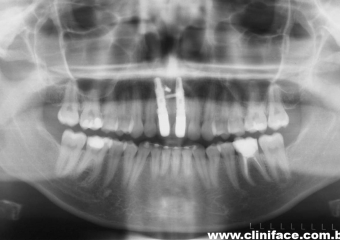

Rx após extração e implantes imediatos